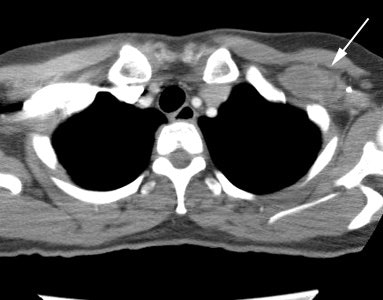

Unsuspected asymptomatic bone metastases: The patient shown below had a history of left breast cancer treated with mastectomy and adjuvant chemo/radiation therapy. The patient presented with a new palpable fullness in the left infraclavicular region. A CT exam revealed a large mass consistent with recurrent tumor (white arrow) and PET imaging was performed for further staging. In addition to uptake in the supraclavicular region (black arrow), PET imaging demonstrated unsuspected, asymptomatic bone metastases to the sacrum, lumbar spine, and left ischium (blue arrows) which were confirmed on MRI (sacrum ischium). |

|